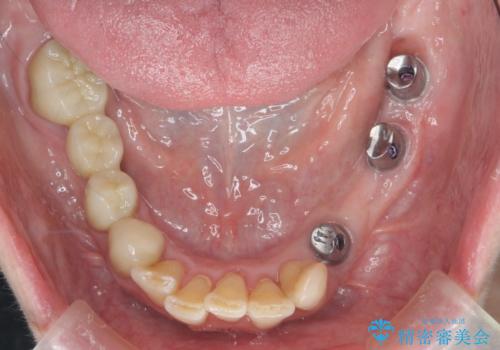

多発した虫歯による咬合崩壊 インプラントを用いた全顎治療

- 「これまで歯の治療をおざなりにしてしまい本当に後悔している。 時間と費用がかかってもいいので、しっかりと安心してかめるような状態にしてほしい。」、と全体的な治療を希望され来院されました。

歯の破折・再発した大きな虫歯・根尖病変・歯の欠損、これらの問題を根管治療・歯周外科・インプラント治療・セラミック補綴を行うことで一つづつ解決し安定した咬合状となるよう治療を進めます。